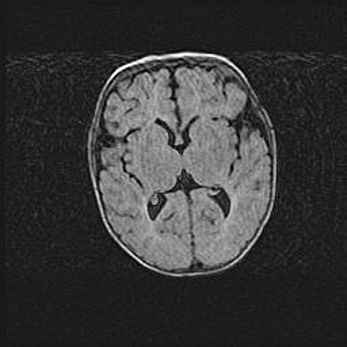

Сообщающаяся гидроцефалия. Кистозная энцефаломаляция головного мозга.

Возраст: 3 месяца 4 дня

Вес: 3100 г

Пол: женский

Окружность головы: 34 см

Срок гестации: 31 неделя

Кистозная энцефаломаляция головного мозга - одна из форм поражения головного мозга в детском возрасте. Характеризуется возникновением множественных и распространённых кист в коре, белом веществе и подкорковых образованиях головного мозга у плодов, новорождённых и детей раннего возраста. Развитие кистозной энцефаломаляции связано с внутриутробной асфиксией и гипотонией, родовой травмой, тромбозом синусов, пороками развития сосудов, инфекциями, сепсисом и другими причинами. Наиболее значимые инфекционные агенты: вирусы простого герпеса, цитомегалии, краснухи, токсоплазмы, энтеробактерии, золотистый стафилококк и другие.